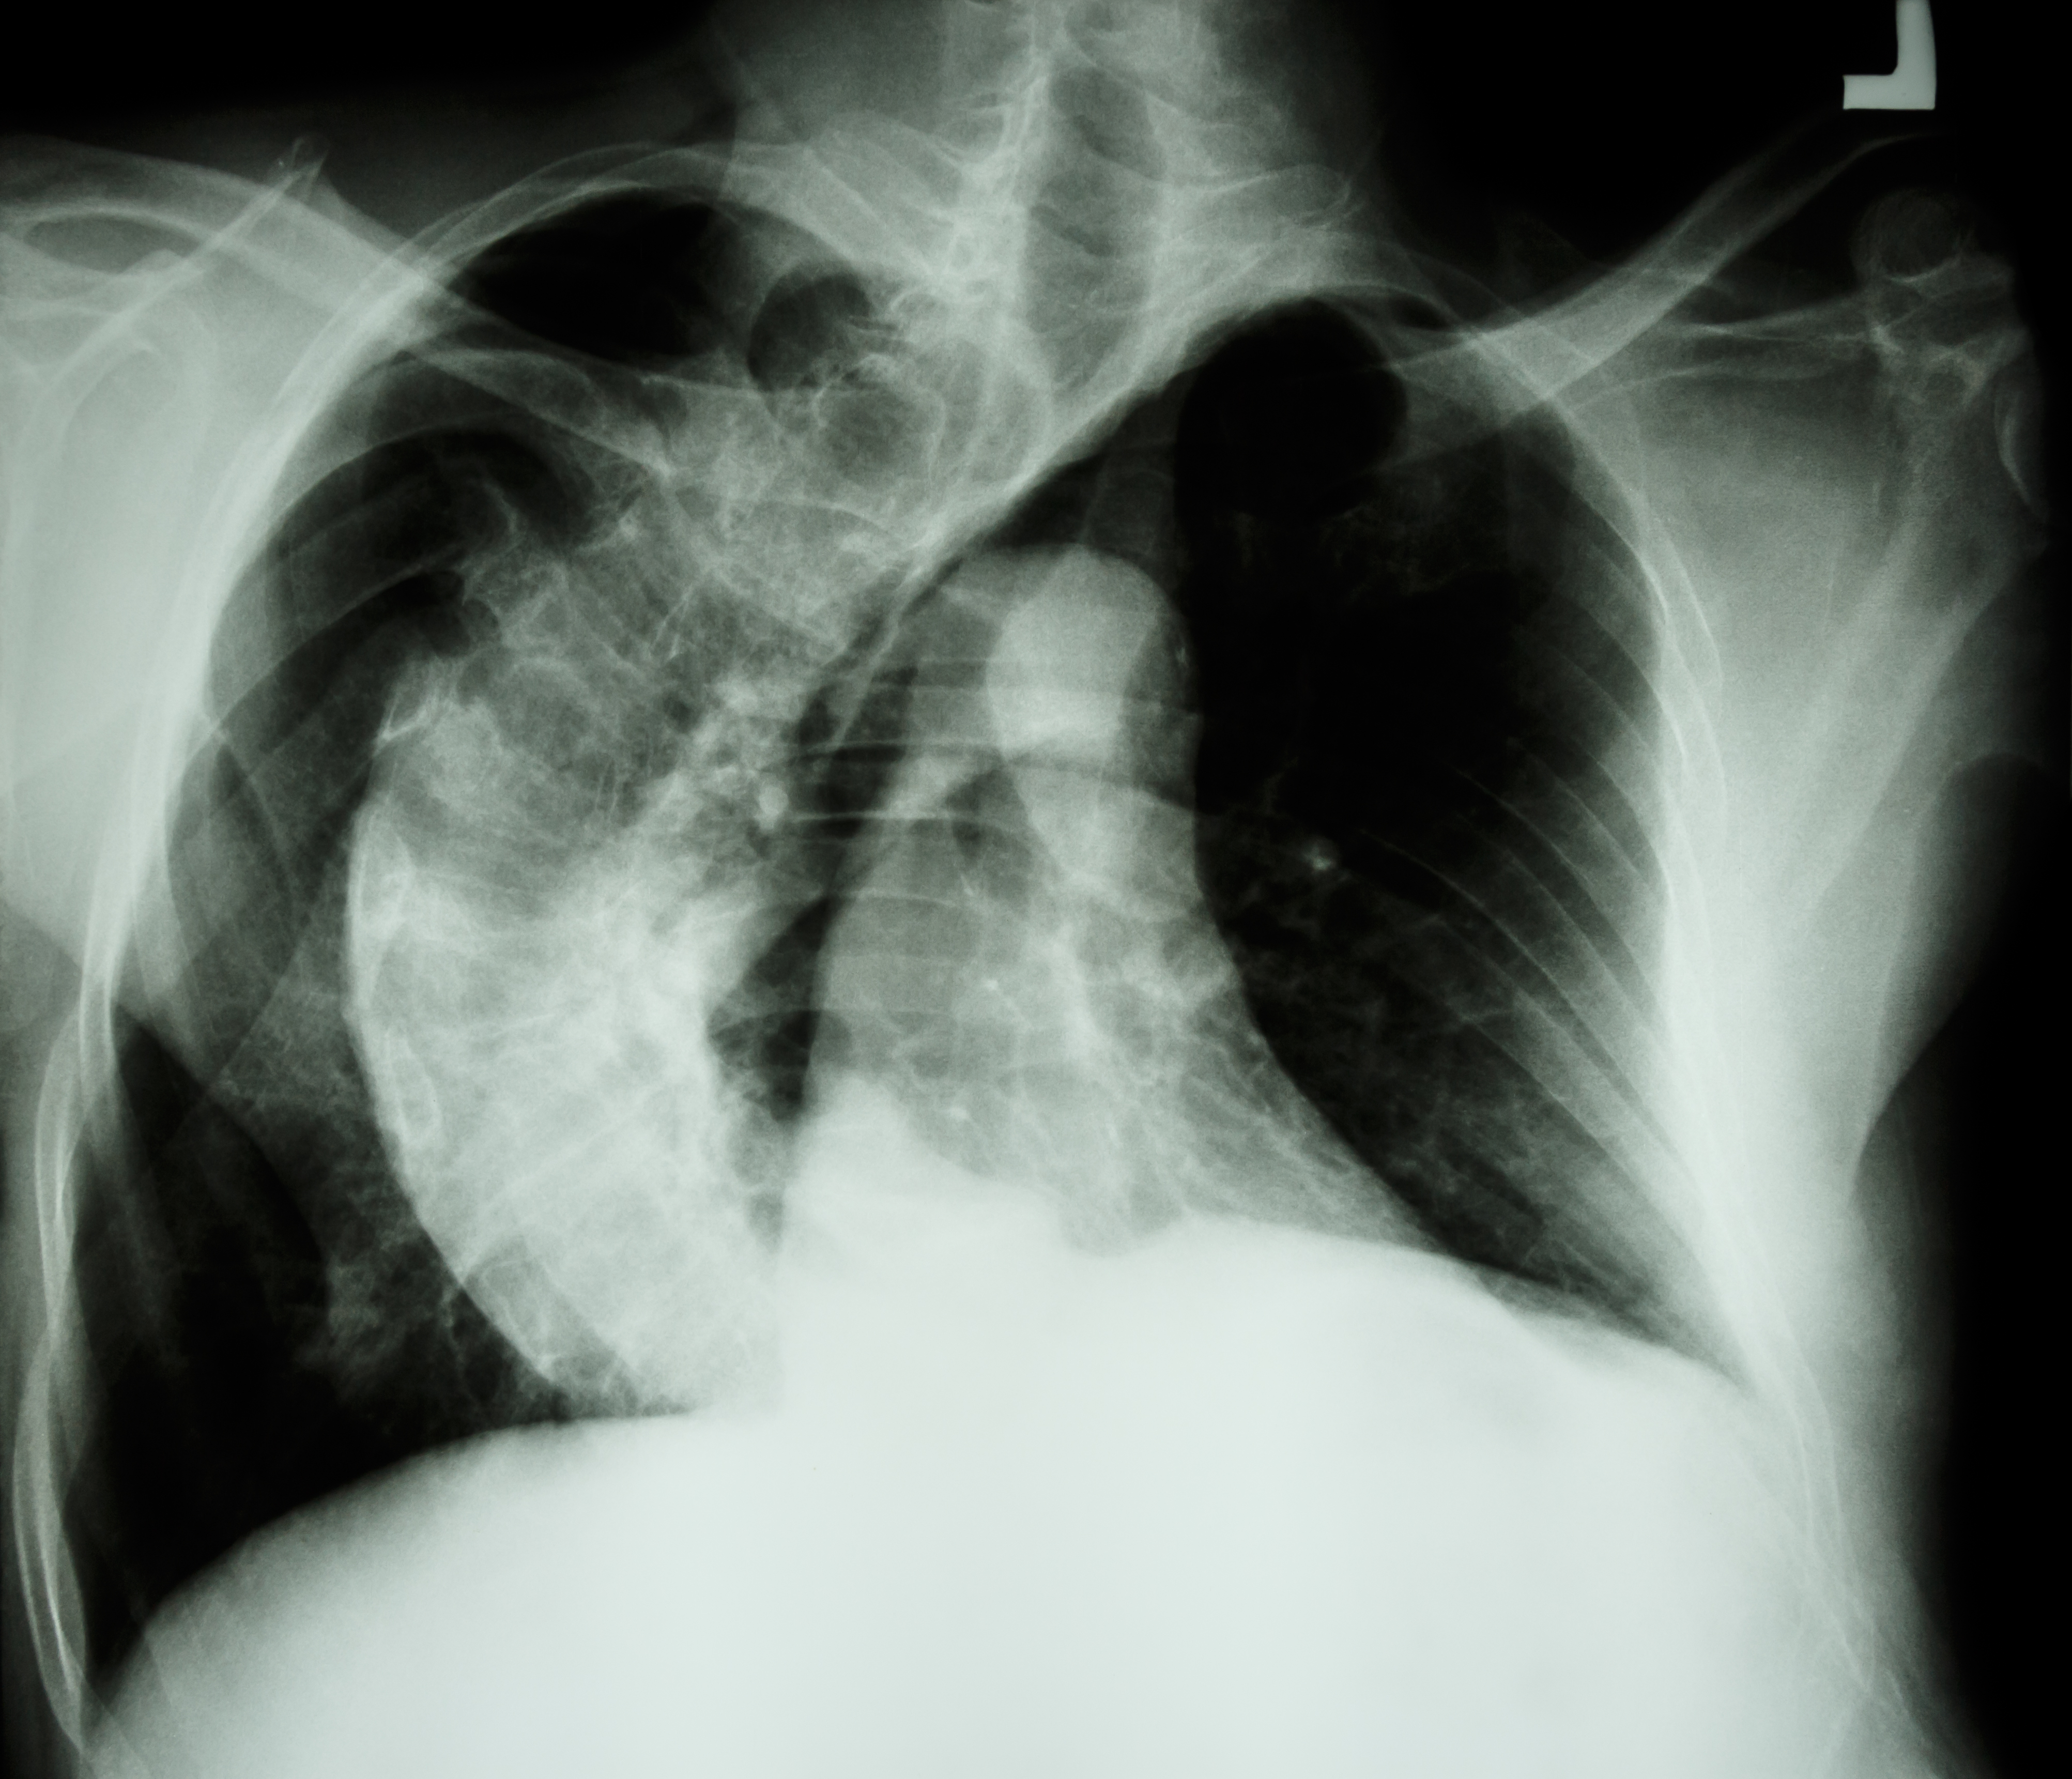

Røntgenbilde av skjev ryggrad.

Illustrasjon: Puwadol Jaturawutthichai / Mostphotos